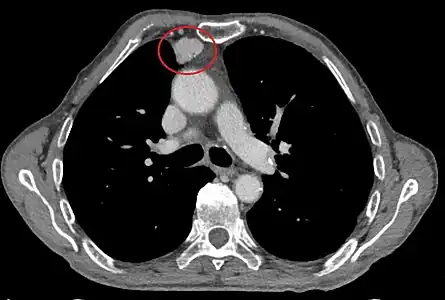

Le scanner thoracique est plus précis que la radiographie thoracique dans le diagnostic des thymomes, en raison d'une plus grande sensibilité envers les masses médiastinales. L'injection de produit de contraste iodé n'est pas forcément nécessaire, mais permet de préciser les rapports du thymome avec les structures vasculaires. Ceci permet à la fois la stadification et de préciser la stratégie chirurgicale lorsqu'elle est envisagée[28].

Les thymomes se présentent comme une masse bien définie du médiastin antérieur, proche du péricarde et dans un plan plus antérieur que les gros vaisseaux intrathoraciques (aorte ascendante et sa crosse, artère pulmonaire, veine cave supérieure). La masse peut être sphérique ou lobulée, mais présente un aspect homogène (plus rarement kystique) qui se réhausse après injection et peut contenir des calcifications[29].

Les critères scanographiques d'envahissement local doivent être recherchés car ils guideront le traitement. D'autre part, l'envahissement scanographique est corrélé au pronostic[30]. L'absence d'un liseré graisseux entre la masse et les vaisseaux, notamment l'aorte et la veine cave supérieure, est un signe d'envahissement local. L'ascension d'une coupole diaphragmatique, comme en radiographie thoracique, est un signe d'envahissement du nerf phrénique[31].

Présentation tomodensitométrique classique d'un thymome à un stade précoce (cercle rouge). À l'arrière, l'aorte, la veine cave supérieure et l'artère pulmonaire sont visibles en coupe.